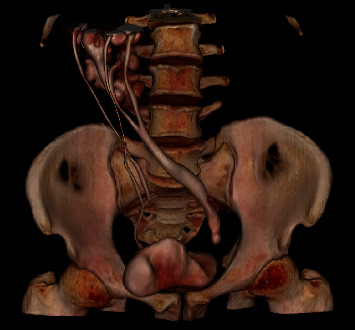

Crossed-fused renal ectopia (CFRE) is a rare congenital anomaly where both kidneys are fused on the same side. We report a case of a 52-year-old male patient who presented with central abdominal pain associated with hematuria and dysuria, with a history of left open ureterolithotomy. Abdominal computed tomography (CT) showed an 18-mm left distal ureteric stone and a CFRE with a bilateral duplex-collecting system. Left ureteroscopy and laser lithotripsy with magnetic double-J stent insertion were carried out successfully, and the patient was discharged on the same day in fair general condition.

Abstract Image